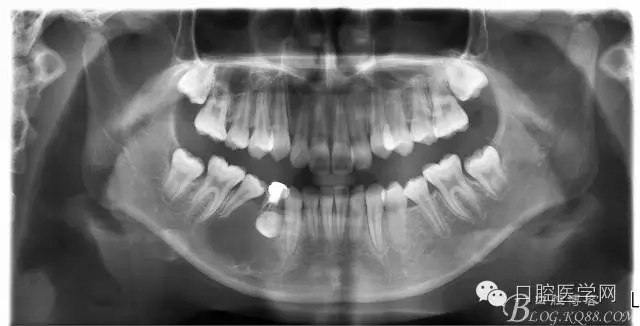

查:右側(cè)第二前磨牙第一乳磨牙恒尖牙頰側(cè)前庭溝隆起,捫有乒乓球感。曲斷及CT示:右側(cè)第二前磨牙第一乳磨牙恒尖牙根尖區(qū)有一囊腫,頰舌側(cè)骨板極薄,牙根無(wú)吸收,第二前磨牙牙根位于囊腫中,第一雙尖牙牙冠遠(yuǎn)中水平向阻生,牙冠位于囊腫中。經(jīng)協(xié)議:手術(shù)摘除創(chuàng)傷大,同意開(kāi)創(chuàng)引流保守治療。

否認(rèn)手術(shù)禁忌癥及過(guò)敏史。消毒,局麻下鋪巾,拔出第一乳磨牙,有囊液溢出,擴(kuò)大開(kāi)放引流孔,取部分囊壁送病理,生理鹽水沖洗,置引流管縫合固定。病理報(bào)告:囊腫。八月后局麻拔除第一雙尖牙刮凈剩余變小的囊壁。

術(shù)后一個(gè)月 三個(gè)月 五個(gè)月 八個(gè)月 拔除第一雙尖牙后 曲斷片: